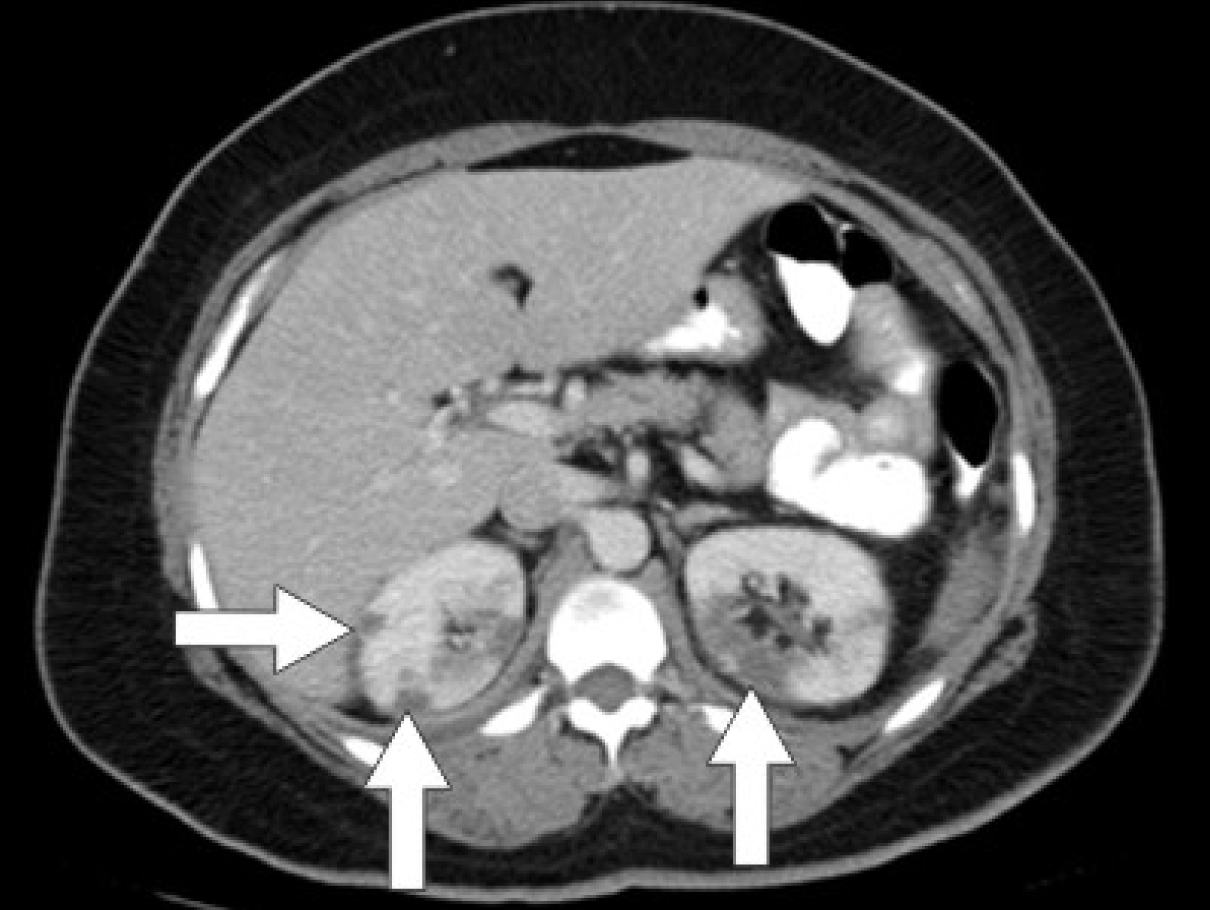

Initial laboratory studies were as follows: WBC 15.47 x 10/mcL, with a neutrophil count of 11.7 x 103/mcL; hemoglobin 13.3 gm/dL; platelet count 33 x 103/mcL; troponin 4.02 ng/mL; total CK 96 ng/mL, with a CK-MB 2.7 ng/mL and a relative index of 2.5; creatinine 0.8 mg/dL; international normalized ratio (INR) 1.56; PT 18.6 second; PTT 34.6 second; fibrinogen 209 mg/dL; fibrin degradation products (FDP) > 20 mcg/mL, and CA125 of 114 U/mL. Urinalysis showed moderate blood. Her EKG showed findings consistent with an acute, non-ST elevation myocardial infarction. CT imaging showed numerous large splenic, wedge-shaped hypodensities (Fig. 1) with similar areas in the kidneys bilaterally (Fig. 2), most consistent with infarcts. Also noted was a 12.4 x 8 x 11 cm right pelvic, complex, cystic and solid appearing mass (Fig. 3). An echocardiogram was obtained and showed mild mitral regurgitation and a moderate sized vegetation on the anterior mitral valve leaflet (Fig. 4). Lower extremity Duplex showed no apparent thrombosis.

![]() Click for large image | Figure 2. CT scan of the abdomen showing wedge-shaped hypodensities in both kidneys bilaterally consistent with renal infarcts. |